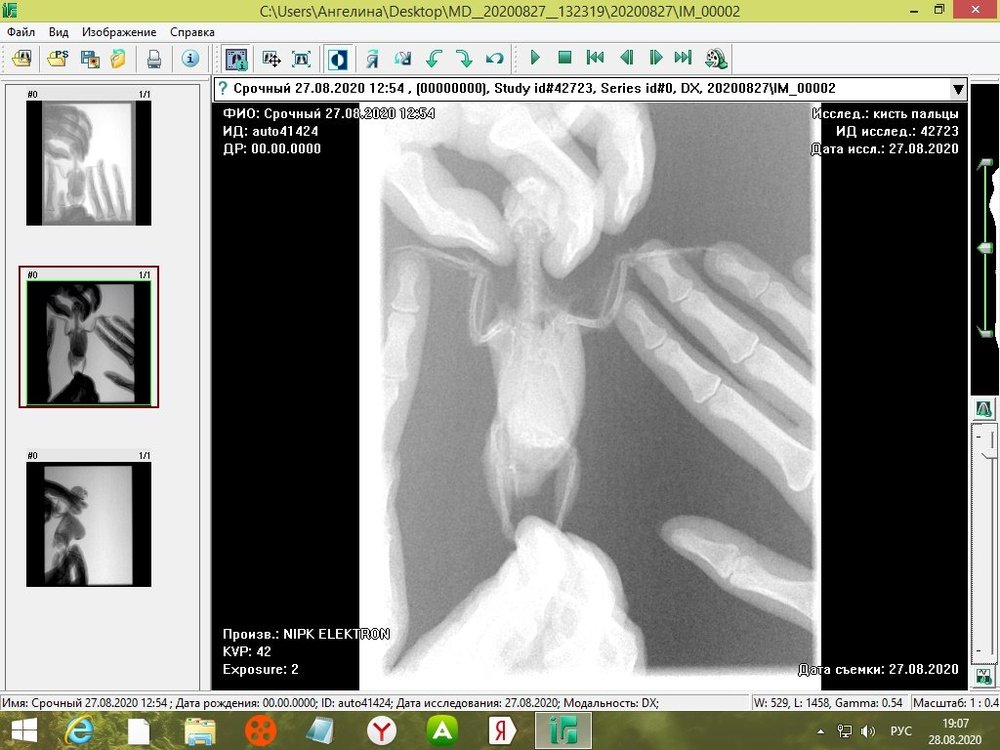

tanushka-sol2020 Опубликовано 27 августа, 2020 Автор #15 Опубликовано 27 августа, 2020 Некадрированные исходные снимки --- щёлкните полосу ниже. Скрытый текст

Кузяныч Опубликовано 28 августа, 2020 #16 Опубликовано 28 августа, 2020 Ох, бедная волнушка... В помёте на шли бактерии (++), слизь (+), жир (+), клетчатку (++)... Есть и непонятные для меня записи... По рентгену на втором снимке справа мне видится что эта огромная припухлость --- растянутый зоб... 18.08.2020 в 17:16, tanushka-sol2020 сказал: Что за опухоль? Она в моих руках меняется: то сморщится, то раздувается как шар надувной... Неужели, действительно зоб?... @tanushka-sol2020, срочно звоните Зосе, просите посмотреть снимки. Мазок из клюва... уф-ф... не знаю пока на сколько он нужен... Если на нистатине птице легче, то давайте его --- придерживайтесь дозировок, что давала вам Зося. Расположите лесенку горизонтально чтоб попугайчик экономил силы. Установите всё как можно ниже к полу. Проверьте, чтоб птичка не пыталась лезть выше и не висла на стенке. Помёт оранжевый... возможно, действительно, печень страдает... Карсил не отменяйте... За гепатовет и как вообще быть я не могу сказать. Нужно чтоб Зося посмотрела рентген. Свяжитесь, пожалуйста, с ней. У меня такое впечатление, что у этой волнушки растянут зоб и от этого плохо уходит и застаивается, протухая, пища.

tanushka-sol2020 Опубликовано 28 августа, 2020 Автор #17 Опубликовано 28 августа, 2020 (изменено) @Кузяныч К сожалению, от нистатина у нее сильно страдает печень. Я не стала ей давать, почти 3 недели принимали. Но срыгивание снова вернулось. Когда я собирала мазок из глотки, она потом срыгнула на одежду. Капли были песочного цвета и консистенция, как каша жиденькая. Но с запахом. Переживаю, вдруг неправильно сделала мазок, впервые же. Во вторнике будет готов анализ. Отпишусь. Рентген делали в больнице, я их кое-как уговорила. Первый "блин с комом", тоже выложила. Вдруг качества нет на снимке, что показал. Завтра Зосе позвоню. Спасибо, что ответили. Эти снимки неудачные выше, племянница скидывала. Я немного контраст отрегулировала, чтобы было видно. Изменено 28 августа, 2020 пользователем tanushka-sol2020